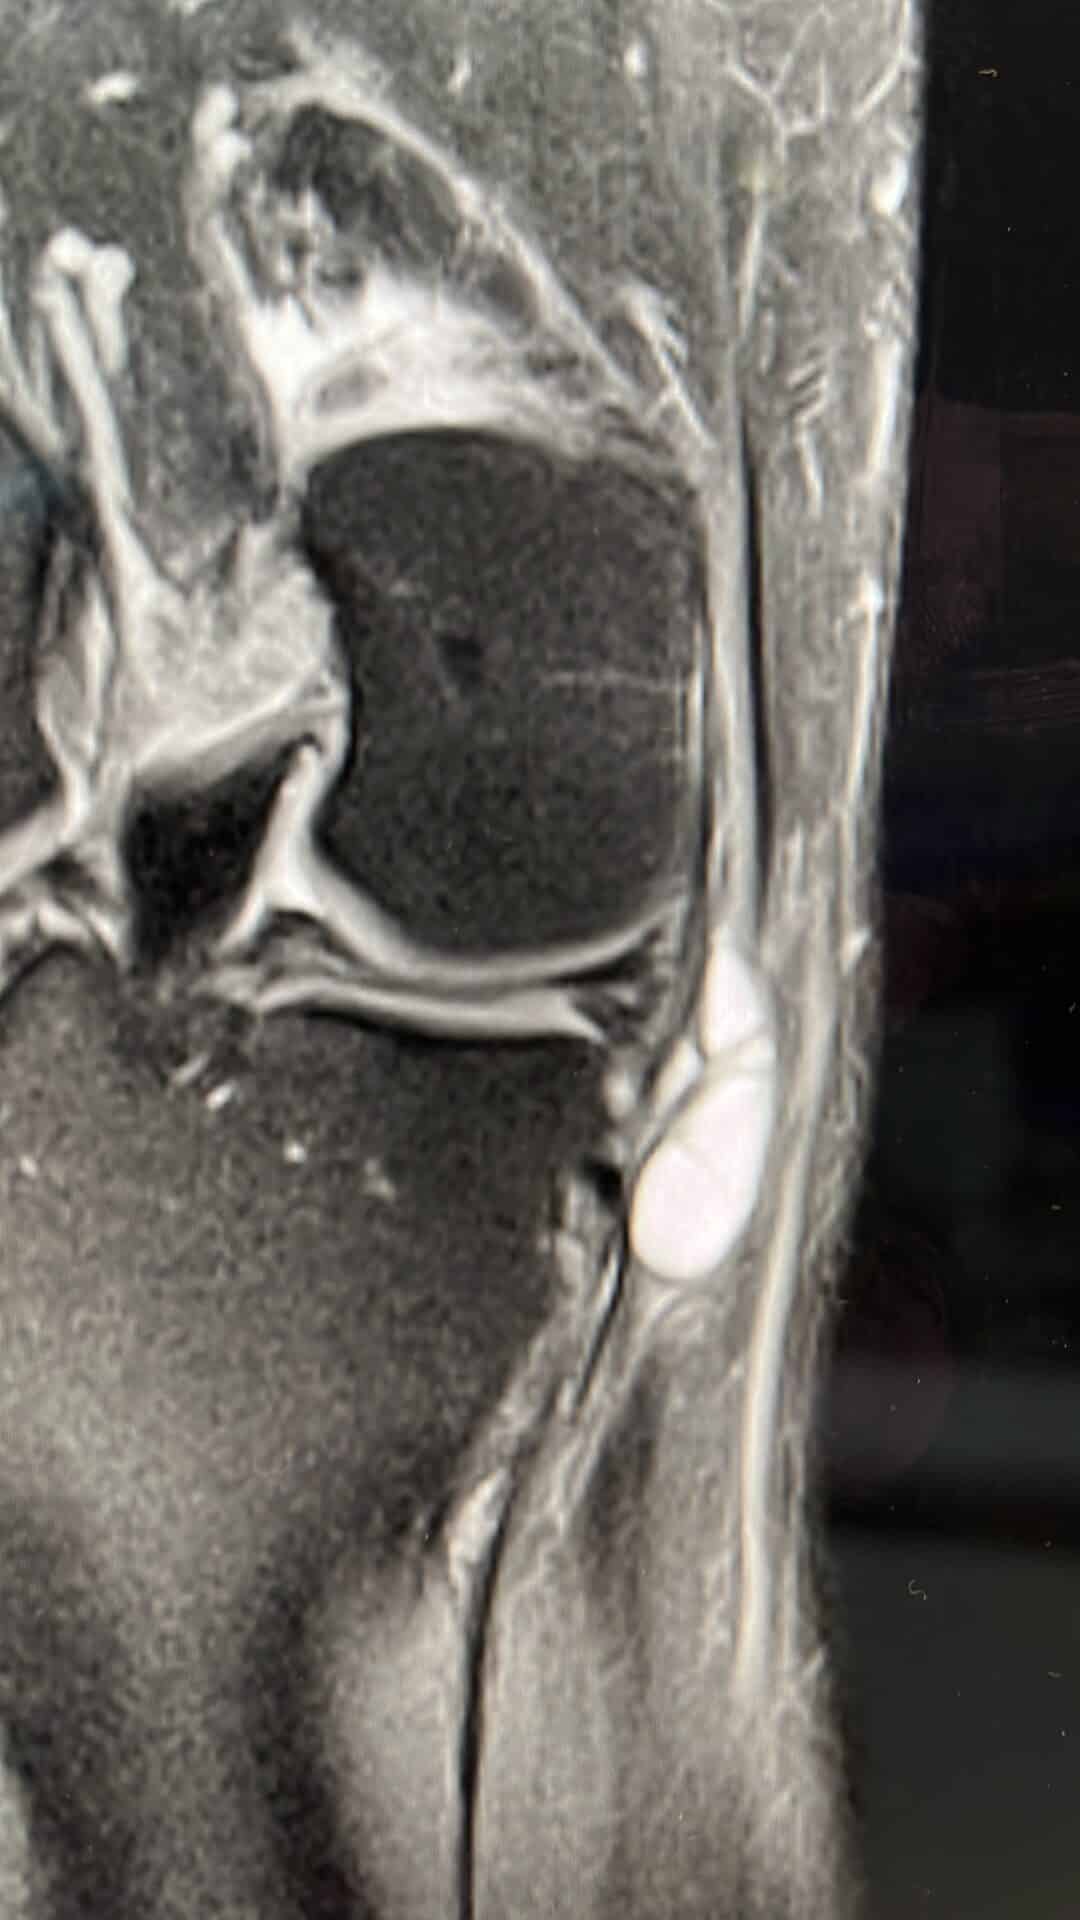

Knieschmerzen gehören zu den häufigsten orthopädischen Beschwerden. Sie können infolge akuter Verletzungen, etwa im Rahmen einer Sportverletzung am Knie, auftreten oder im Verlauf degenerativer Prozesse zunehmen, wie z.B. bei einer Arthrose im Knie. Auch ein Meniskusriss stellt eine häufige Ursache funktioneller Einschränkungen dar.

Knieschmerzen äußern sich häufig durch belastungsabhängige Beschwerden, Bewegungseinschränkungen, Schwellungen oder Instabilitätsgefühl. Beschwerden beim Treppensteigen oder nach längerem Sitzen sind ebenso typisch wie Reibegeräusche oder morgendliche Steifigkeit.

- Traumatische Ursachen: Verletzungsfolgen wie Meniskusriss, Bandrupturen (z. B. Kreuzband), Sehnenverletzungen – häufig im Rahmen einer Sportverletzung am Knie

- Degenerative Veränderungen: Gelenkverschleiß (Arthrose) mit Abnutzung des Knorpels, oft verstärkt durch eine Fehlstellung der Beinachse, beispielsweise O-Beine (Varus) oder X-Beine (Valgus)